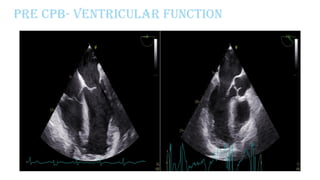

Pre CPB- Ventricular function

PRE CPB TEE

oFair LVSF; EF - 30%, CO - 2.8L/m, CI - 1.4L/min/m2

oFair RVSF; RVEF - 26%, RVFAC - 24%, TAPSE – 11 mm

oApical VSR+,

oIt is a complex VSR at the apical ventricular septal level showing

multiple jets across the thin apical septum.

oQp/Qs=2.0

oRWMA+; Apex thinned out. Akinesia of mid mid-anterior and inferior

wall

oMild TR; Mild PAH (RVSP=46)

oMild MR